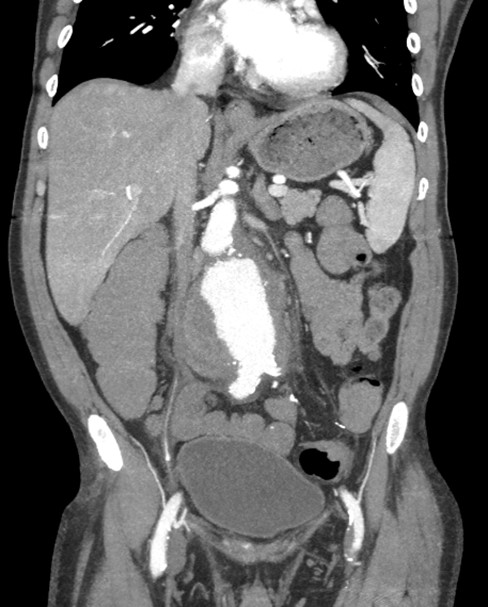

A 56-year-old Caucasian male, with prior history of chronic obstructive pulmonary disease and nicotine dependence presented to the hospital with shortness of breath, productive cough, with fever and chills. He was found to be in acute exacerbation secondary to right basilar pneumonia and initiated on treatment. As part of the initial workup, computerized tomography (CT) scan of the chest and abdomen was also ordered, which revealed an incidental finding of an infrarenal abdominal aortic aneurysm, measuring 5.1 x 5.1cm x 10.4cm. Blood cultures ordered on admission returned positive for Salmonella enteritidis, which was sensitive to ceftriaxone, and appropriate antibiotic treatment was initiated.

The patient subsequently began to develop abdominal discomfort and new fever spikes. Repeat lab findings showed an increased leukocyte count, and CT angiogram demonstrated a significantly increased size to 7.6 x 9.1 x 13.3cm, concerning for impending rupture and underlying aortitis. Nuclear white blood cell scan was performed and revealed abnormal increased uptake involving the mid and distal abdominal aorta, suggestive of infection. Vascular consultation was obtained, and he successfully underwent percutaneous endovascular aortic repair. He tolerated the surgery well and observed improvement in symptoms, following which he was discharged.

Image 1: Abdominal CT scan with contrast (Coronal plane) demonstrating Abdominal aortic aneurysm.